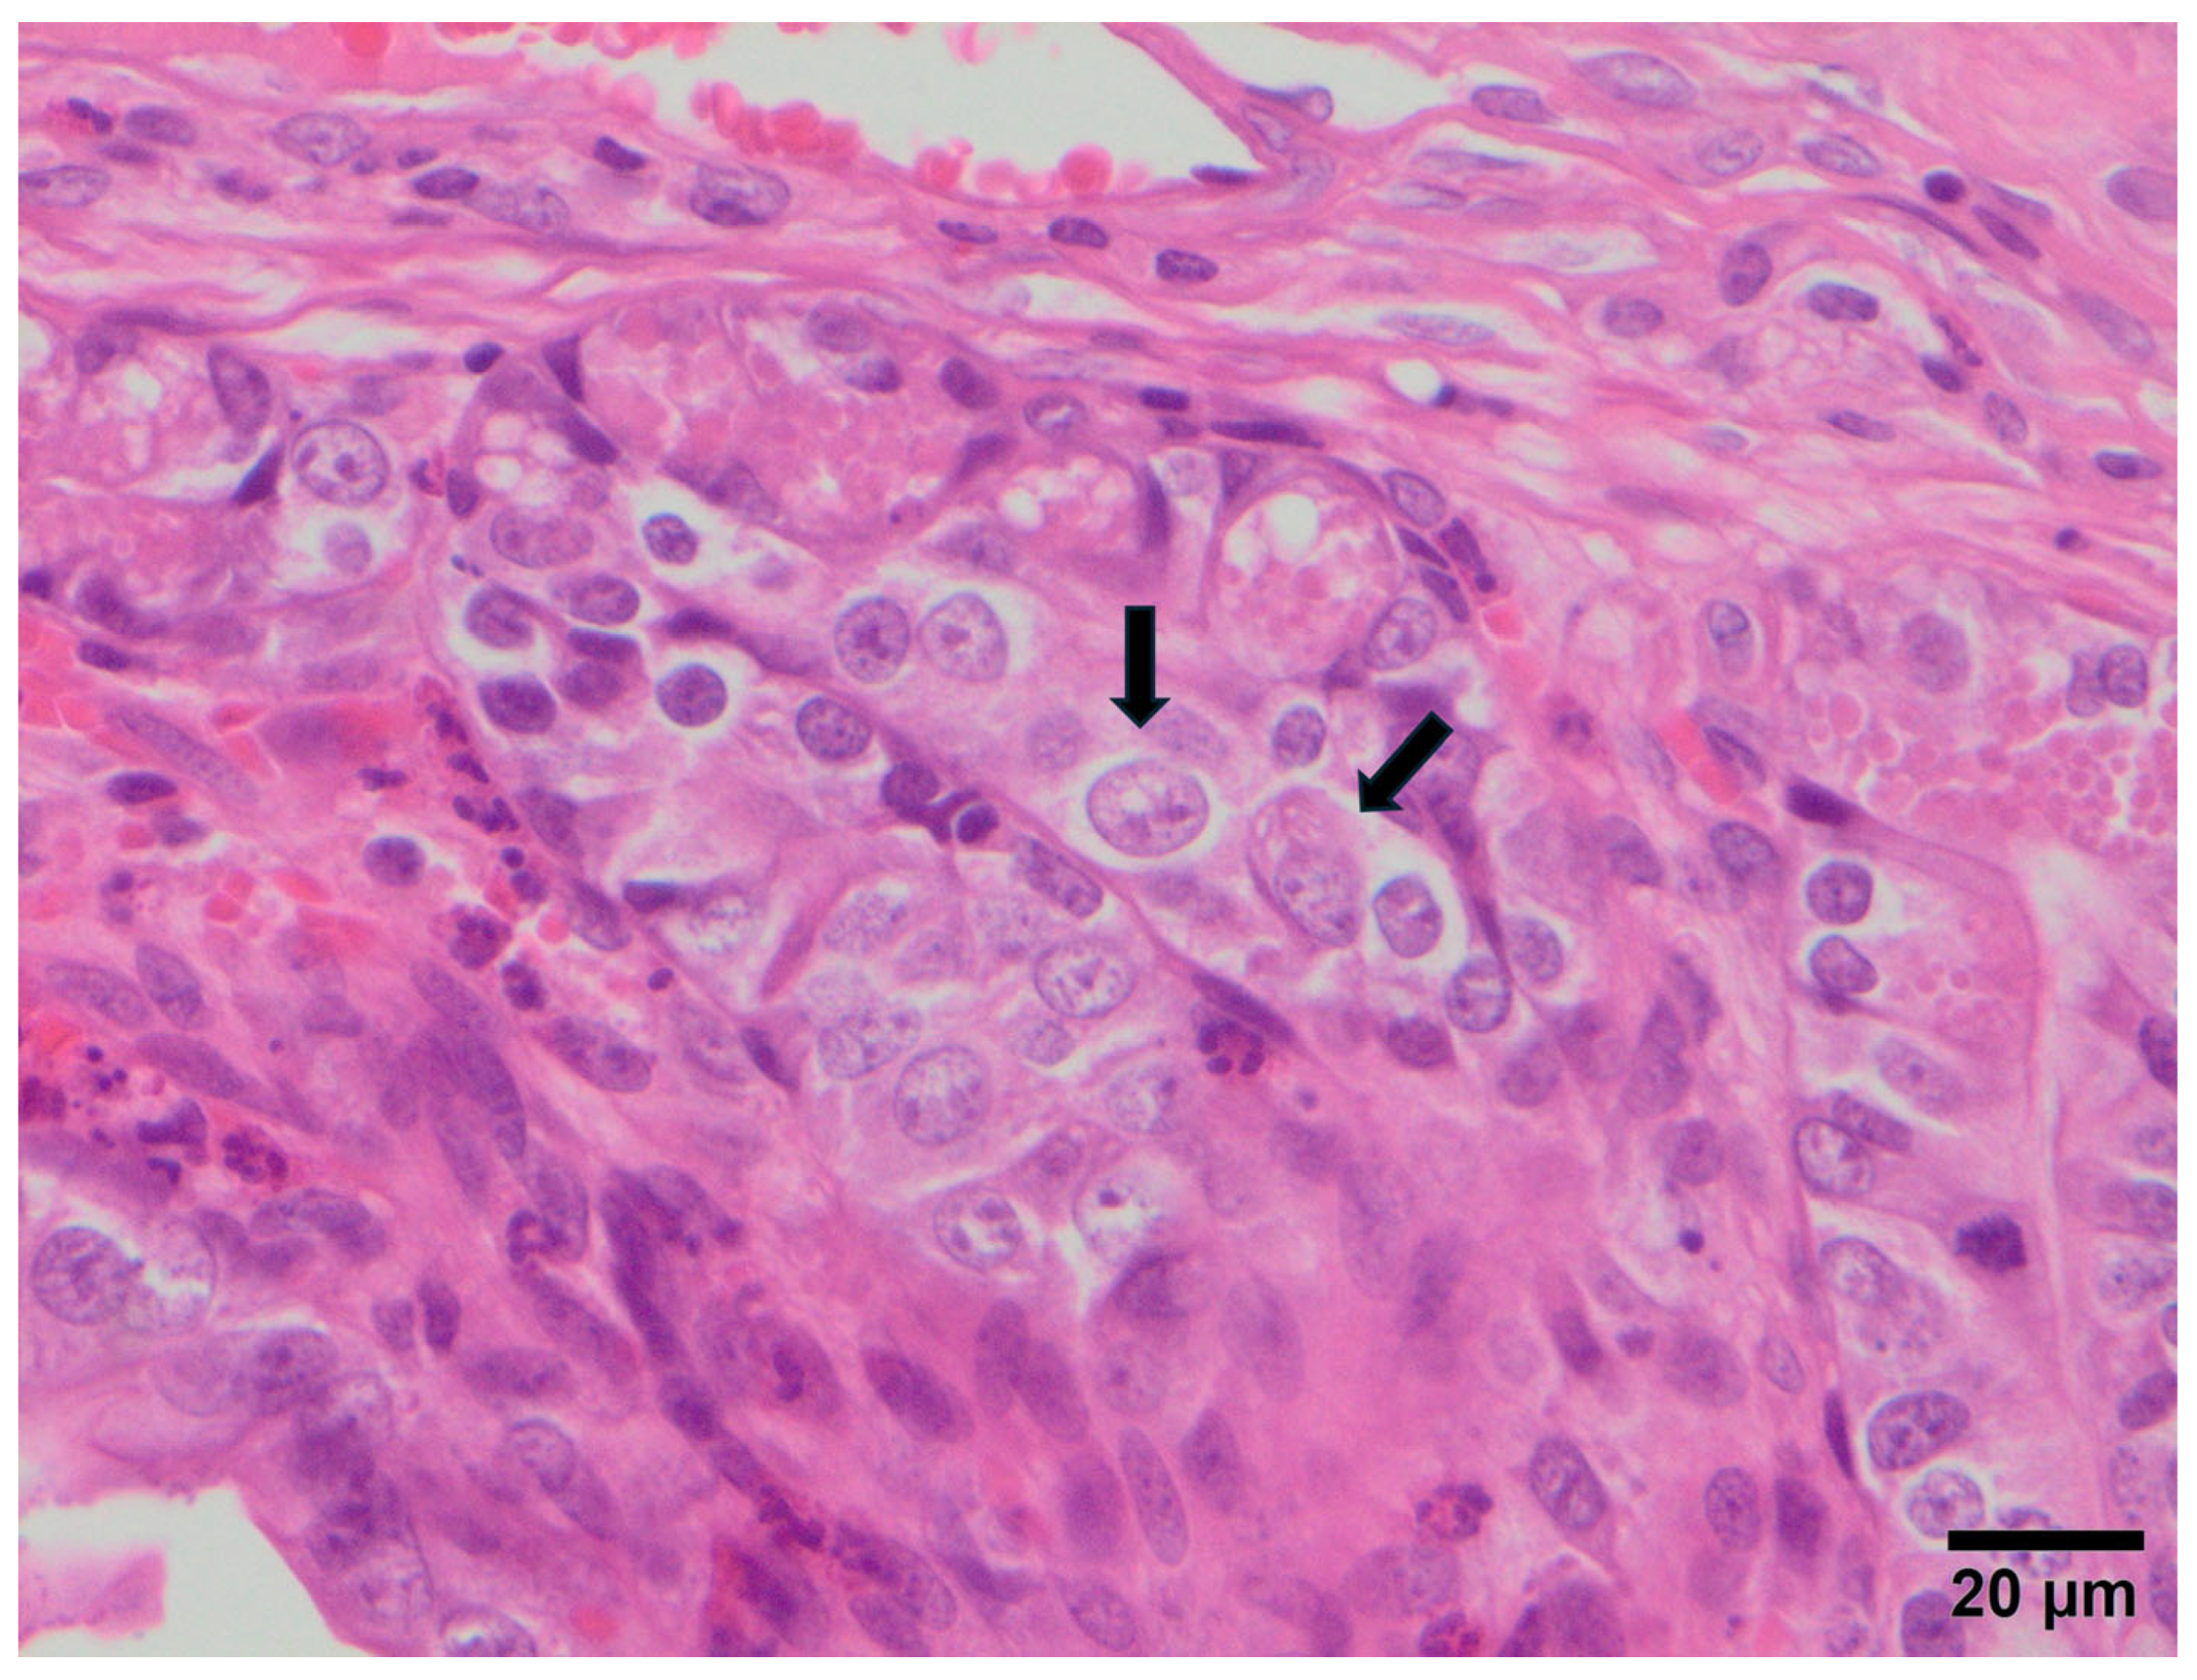

3.2. Study B: Lesional Study